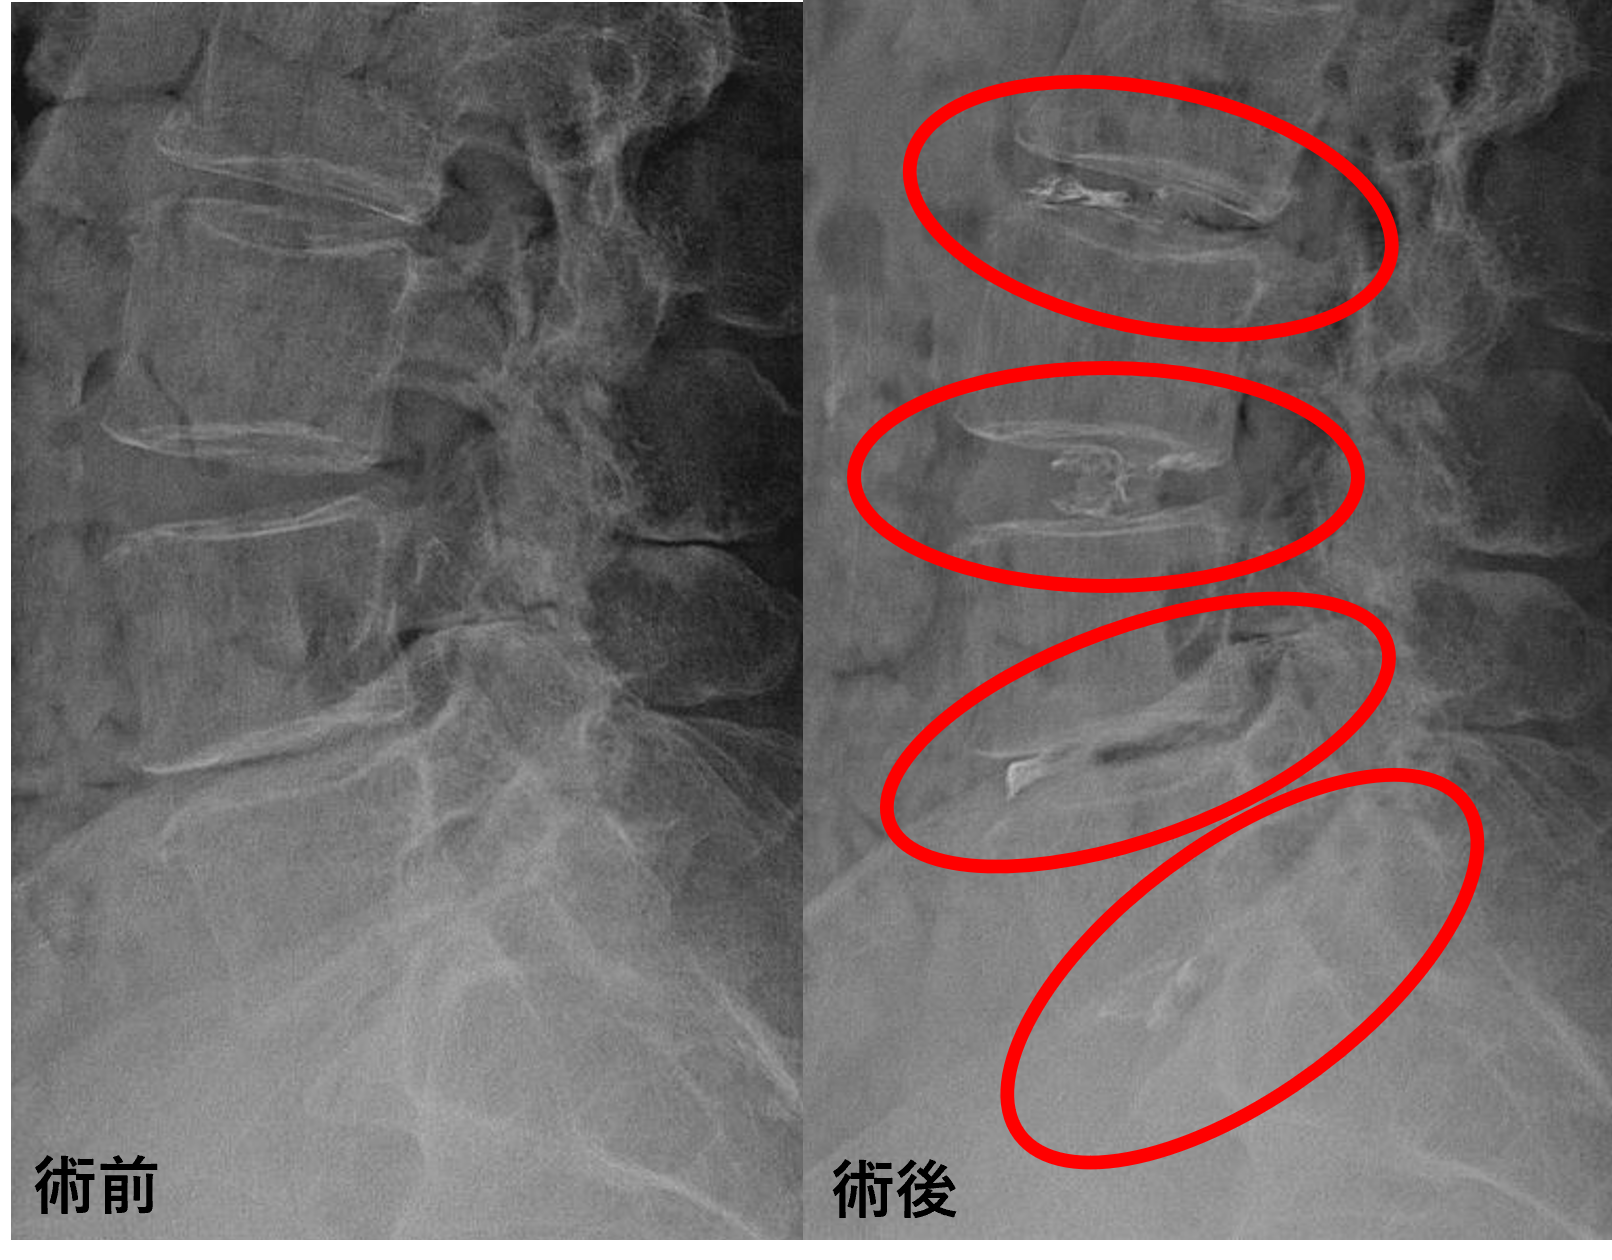

画像及び所見について

- L3/4 – 椎間板変性、膨隆

- L4/5、5/s – 椎間板変性、膨隆、椎間孔狭窄

以上のことが画像上認められました。

L2/3、3/4、4/5、5/sの椎間板所見による脊柱管の圧排が、症状の原因の可能性が高い。

患者様と相談の元、L2/3、3/4、4/5、5/sにセルゲル法を施行